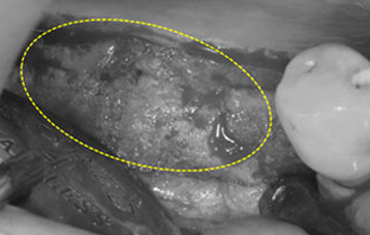

타 치과의 뼈 이식 후 골조직

램브란트치과 상인점 뼈이식 후 골조직